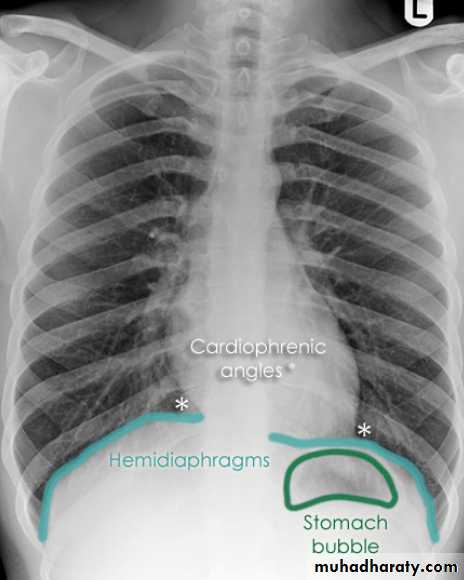

CXR of adult male PA and lateral views, it shows :Normal both lung fields ,Central cardiac shadow, Central trachea, central mediastinum, No boney lesions, no soft tissue abnormalitiesnormal radiologic anatomy of the chest Look carefully on both diaphragmatic cruse costo & cardio phrenic angles. Useful in detection of pleural effusion

Upper zone>>>> 1st and 2nd ribsMiddle zone>>>> 3rd and 4th ribsLower zone>>>> 5th and 6th ribsHow to asses cardiac size We take 2 lines the between borders of cardiac shadow and 2 lines between the inner surface of thoracic cage and the ribsCardiothoracic ratio (CTR) =Cardiac Width : Thoracic WidthA CTR of greater than 1:2 (50%) is considered abnormal.